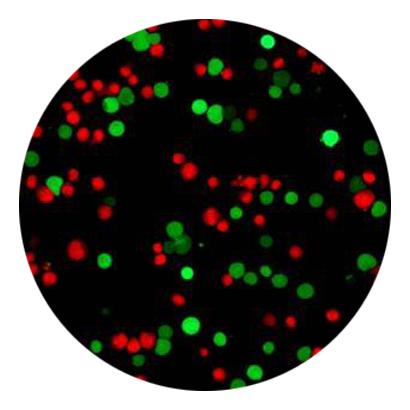

细胞活死染色